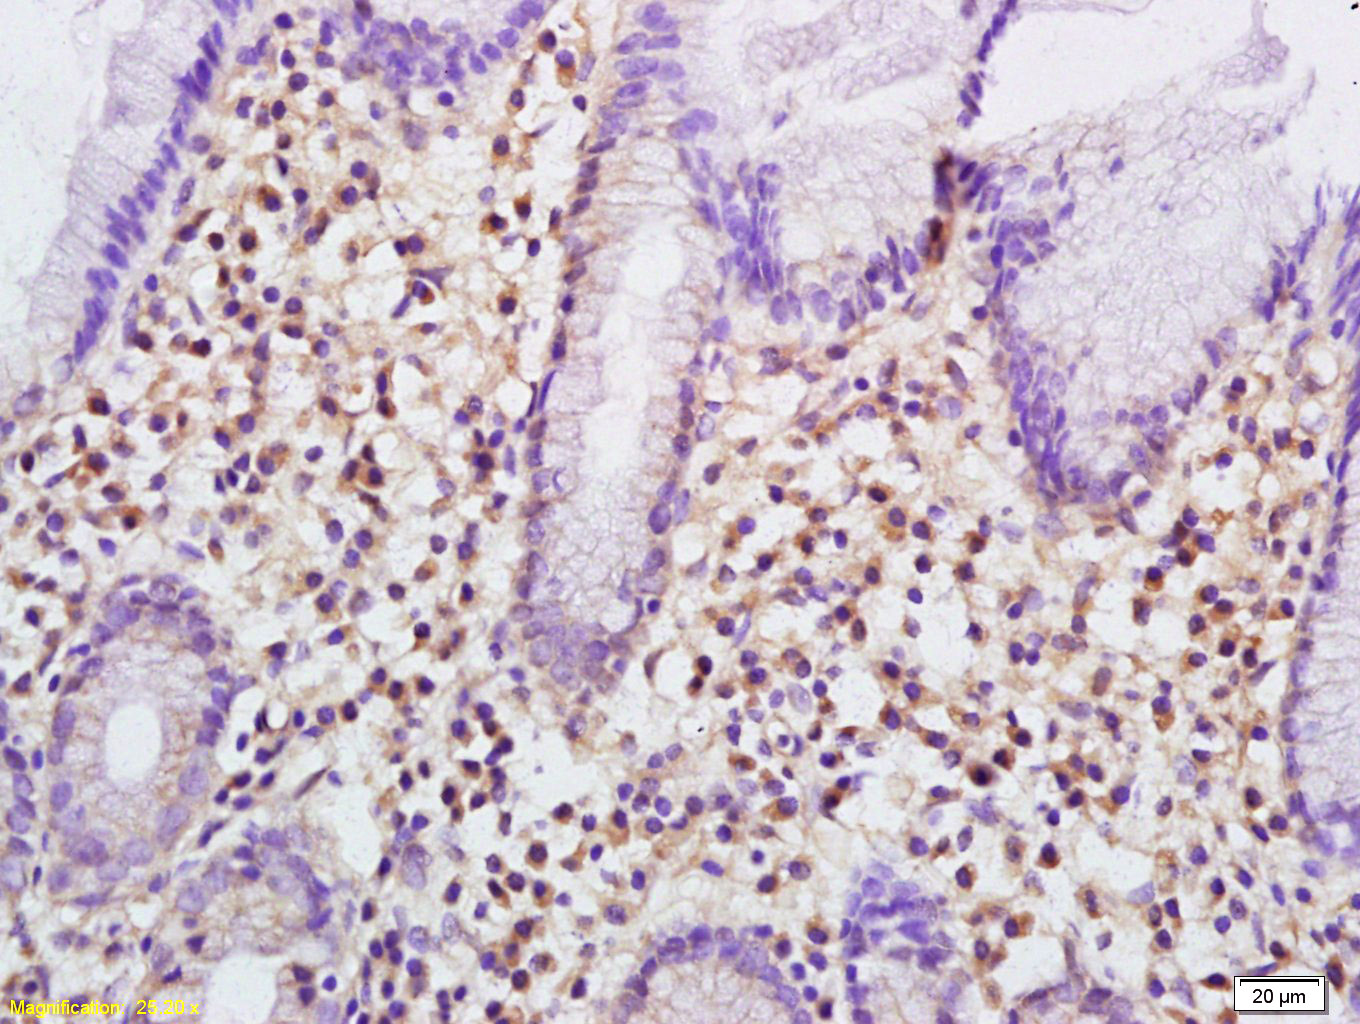

Tissue/cell: human gastric carcinoma; 4% Paraformaldehyde-fixed and paraffin-embedded; Antigen retrieval: citrate buffer ( 0.01M, pH 6.0 ), Boiling bathing for 15min; Block endogenous peroxidase by 3% Hydrogen peroxide for 30min; Blocking buffer (normal goat serum,C-0005) at 37℃ for 20 min; Incubation: Anti-Plastin L Polyclonal Antibody, Unconjugated(bs-7005R) 1:200, overnight at 4°C, followed by conjugation to the secondary antibody(SP-0023) and DAB(C-0010) staining